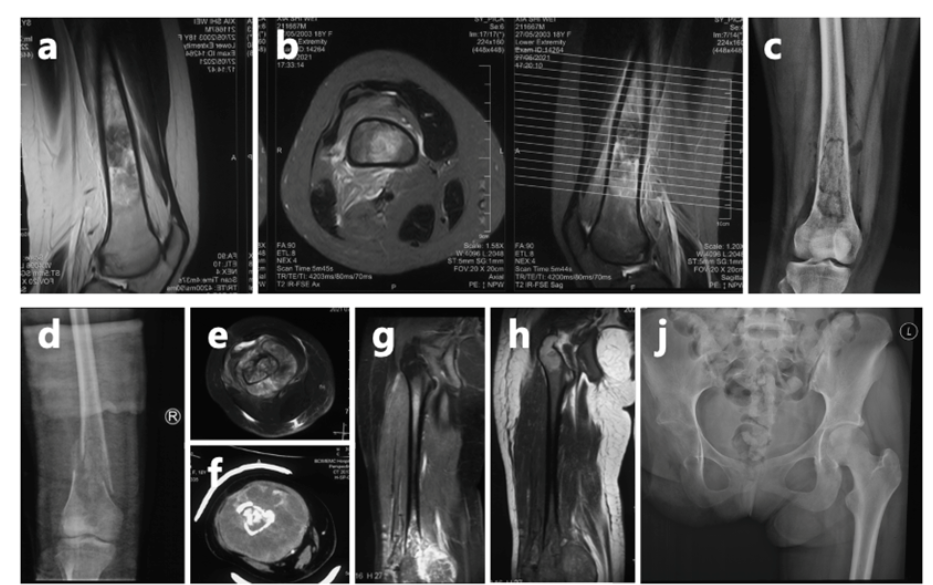

18岁确诊骨癌,19岁截肢,23岁面临多处转移。 这就是夏夏过去五年的青春。肺叶切除,六次大手术,无数次化疗。为了“活下去”这个简单的愿望,她付出了常人难以想象的代价。

上海市第一人民医院骨肿瘤科讲述了夏夏的最新情况:她经历了6次手术和无数次挑战,自2023年8月接诊以来,又完成了10次化疗和2次手术。尽管困难重重,她始终以微笑和坚韧面对一切。

夏夏前期接受了术前化疗、截肢手术及术后化疗,使用的是一线化疗方案。然而,结疗不到一年,肺部出现转移病灶,经过手术切除后未再进行化疗。术后5个月,左肺再次发现新发转移病灶。

2024年11月,夏夏接受胸腔镜下右肺下叶切除术。2025年1月复查:右肺术后改变。